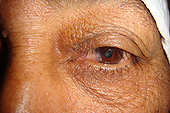

Severe ectropion of the lid as well as eversion of the tear duct (inner corner of lid)

Immediately after ectropion and tear duct repair. Improved position of lid and tear duct